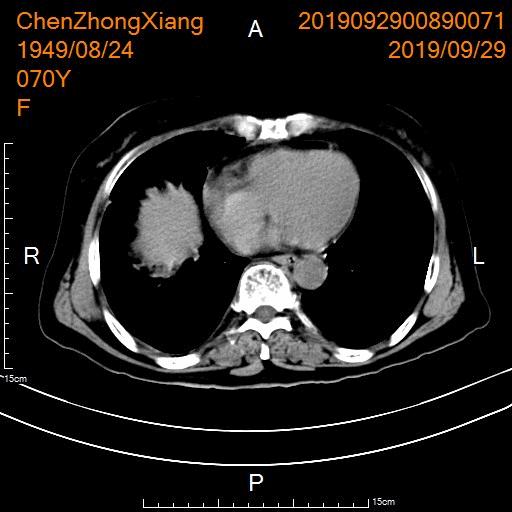

- 后续行胃癌及肝转移瘤动脉化疗灌注+肝动脉载药微球栓塞

行胃癌及肝转移瘤动脉化疗灌注+肝动脉载药微球栓塞

- 术后复查CT显示肝转移瘤明显坏死

CT显示肝转移瘤坏死